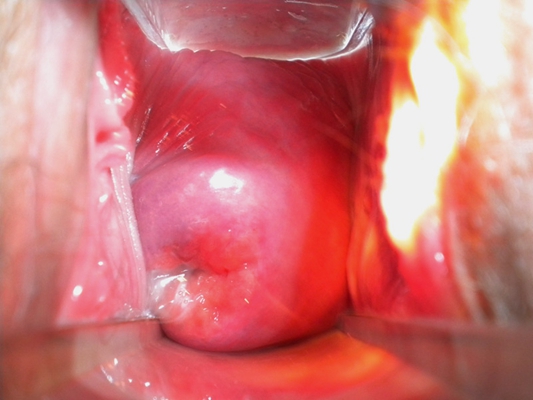

子宮頸癌圖片

宮頸癌

宮頸癌

宮頸癌

宮頸癌

宮頸癌

宮頸癌

宮頸癌

宮頸癌

宮頸癌

宮頸癌

宮頸癌

宮頸癌

宮頸癌

宮頸癌

宮頸癌

宮頸癌

宮頸癌

宮頸癌

宮頸癌

宮頸癌